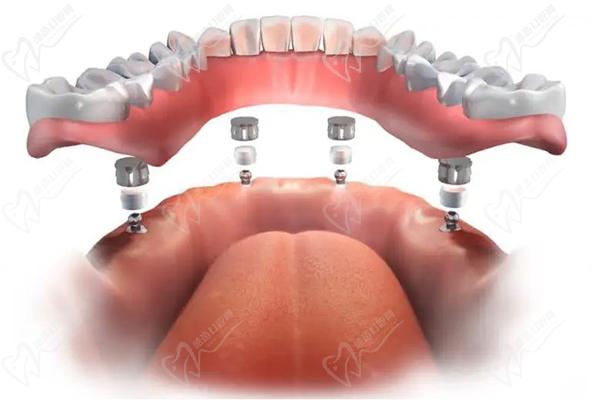

半口種植牙·集采種牙:21860元起

全口種植牙·集采:42720元起